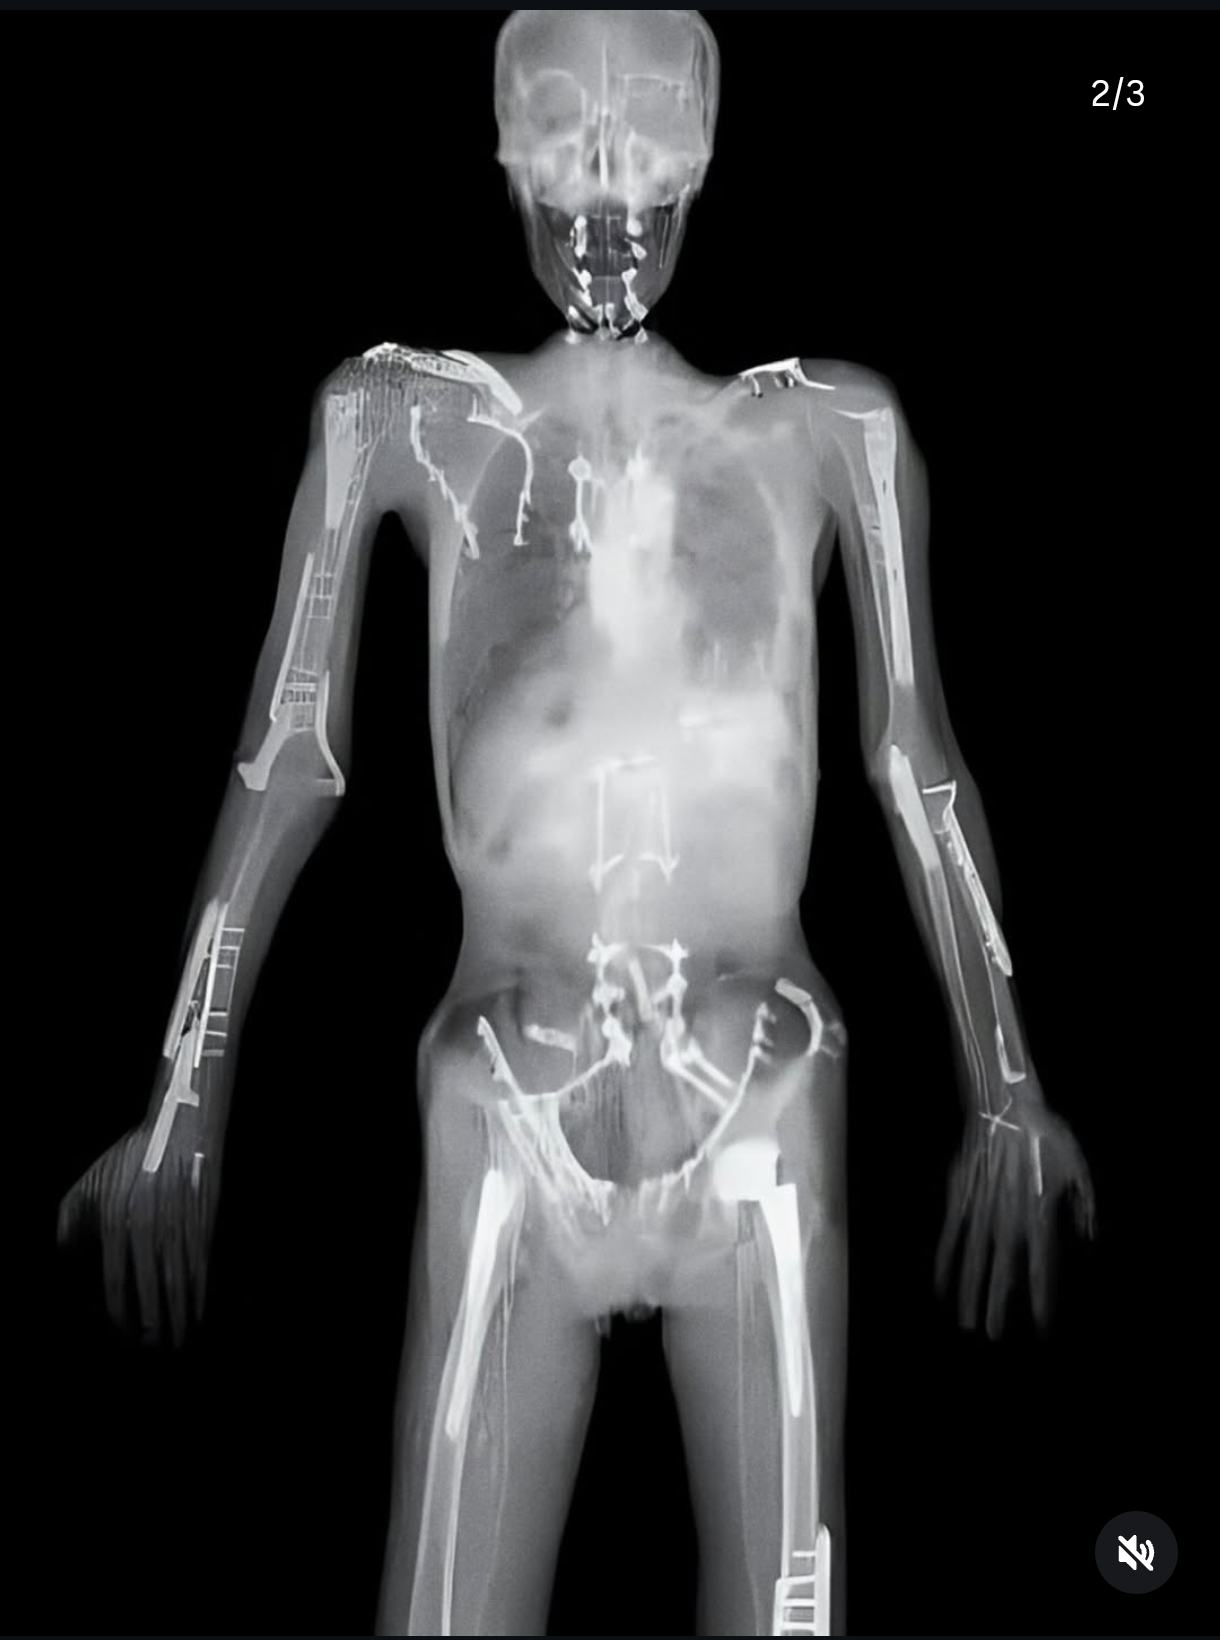

Obrázek Uhodni sport 1ze2

Souhrnný rentgen Sledge bobistů

nefaktčekoval jsem. A viral X-ray of stuntman Travis Pastrana shows metal plates, screws, and evidence of countless fractures accumulated over years of extreme sports. His body is essentially held together by hardware, a visible record of the physical toll that comes with a career built on high-risk stunts.